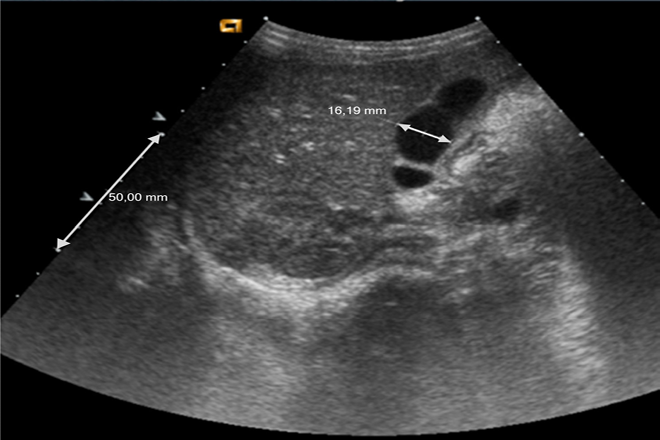

Ultrasonido renal

El ultrasonido renal es una técnica de evaluación por imagen que sirve para valorar la imagen del riñón y sus patologías. En ciertas ocasiones no es posible una buena visualización del riñón por lo que ala urografía excretora es un medio de diagnostico de apoyo.